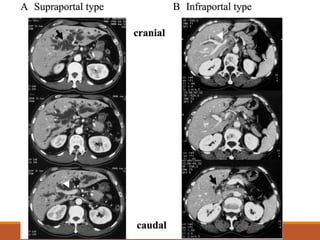

• #30 Confluence patterns of the right posterior sectional bile duct (RPSBD). (A); Supraportal type, the RPSBD runs cranially around the RPV to form a confluence with the right anterior sectional bile duct (RASBD) duct at cranial side of the RPV. (B); Infraportal type, the RPSBD runs caudal to the RPV and joins to the RASBD at caudal side of the RPV. (C); Combined type, there is no RPSBD. The ducts from segments 6 and 7 have separate confluences with the remaining biliary tree; one segmental duct runs in a supraportal position and the other in an infraportal position. Bl, left hepatic duct; Br, right hepatic duct; B6, segment 6 duct; B7, segment 7 duct; PV portal vein.

• #31 Diagnosis of the confluence pattern of the right posterior sectional bile duct (RPSBD) using contrast enhanced computed tomography. (A); Supraportal type, the RPSBD (arrow) joins to the distal bile duct at cranial side of the right portal vein (RPV) (arrowhead). (B); Infraportal type, the RPBD (arrow) joins to the distal bile duct at caudal side of the RPV (arrowhead)